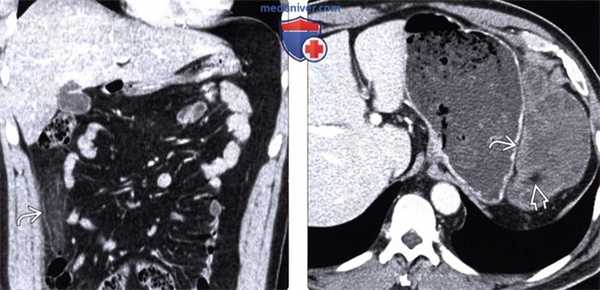

(Левый) При УЗИ в черно-белом режиме определяется четко отграниченное эхогенное образование с гипоэхогенным ободком утолщенной висцеральной брюшины и нечеткими гипоэхоген-ными очагами в центре. Обратите внимание на отсутствие изменений гипоэхогенных слоев, представляющих собой собственную мышечную оболочку сигмовидной кишки.

(Правый) При цветовой допплерографии отмечается отсутствие сосудистой сети образования.

(Левый) У этого же пациента при КТ с контрастным усилением на аксиальной томограмме определяется типичная рентгенологическая картина аппендажита с исчерченностью окружающей жировой клетчатки. Обратите внимание на отсутствие изменений прилегающей сигмовидной кишки.

(Правый) При мульти планарной реконструкции в соответствующей корональной плоскости определяется воспаленный сальниковый при весок; видна его тесная связь с неизмененной прилегающей сигмовидной кишкой.

(Левый) У пациента с подозрением на дивертикулит при КТ с контрастным усилением определяется образование, содержащее жировую клетчатку, периферия образования характеризуется повышенным коэффициентом ослабления (симптом кольца), в центре визуализируется линейный участок повышенной плотности (эквивалент симптома центральной точки в проекции еп face). Обратите внимание на исчерченность окружающей жировой клетчатки.

(Правый) Этот же пациент. Контрольное КТ с контрастным усилением восемь месяцев спустя. Отмечается улучшение, но рентгенологические изменения все еще сохраняются. Этот случай иллюстрирует медленное разрешение рентгенологических изменений при аппендажите.